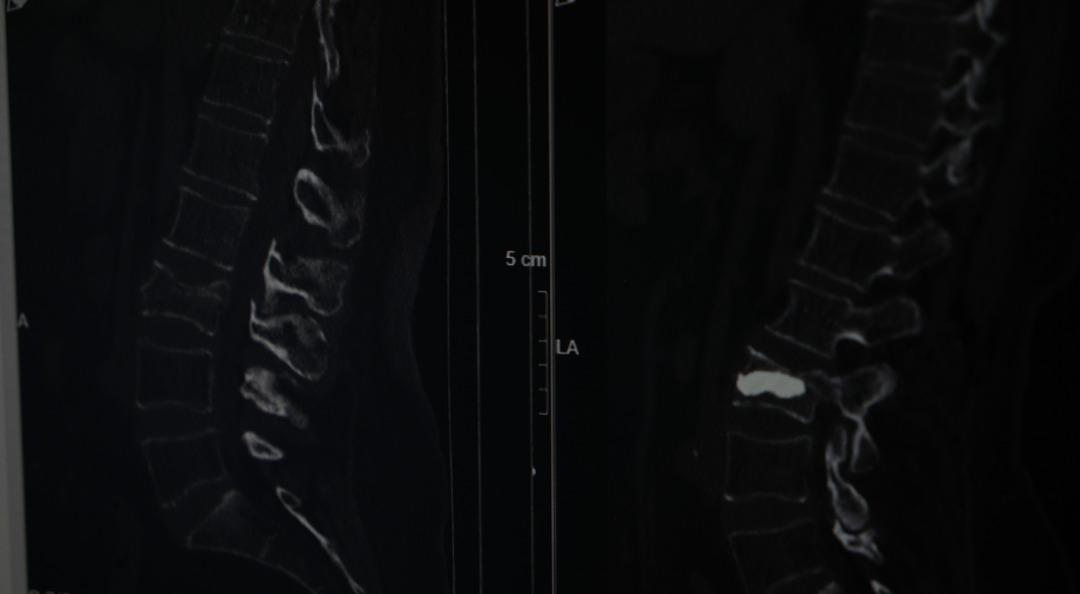

Bir süre bu şekilde düşünen Armağan, ağrıları geçmeyince Şişli Hamidiye Etfal Eğitim ve Araştırma Hastanesi'ne başvurdu. Burada Beyin ve Sinir Cerrahisi Uzmanı Doç. Dr. Şevket Evran ve ekibinin yaptığı incelemelerde kemik erimesine bağlı kırık tespit edildi. Armağan, durumu şaşkınlıkla karşılarken doktorlar operasyon gerekliliğini ifade etti.

Genellikle kemik erimesine bağlı omurga kırıklarını tedavi etmek amacıyla uygulanan minimal invaziv bir cerrahi yöntem olan ve hastanın aynı gün normal yaşamına dönebilme imkanı sunan kifoplasti operasyonu 25 Ağustos günü gerçekleştirildi. Doç. Dr. Evran ve ekibinin yaptığı operasyon başarılı geçerken Armağan da rahat bir nefes aldı. Doç. Dr. Evran, özellikle menopoz sonrası kadınlarda kemik erimesi kaynaklı oluşan kırıklarına dikkat çekerken tedavilerine ilişkin bilgi verdi, vatandaşlara önemli uyarılarda bulundu.

"Omurga kırıklarını menopoz sonrası bayanlarda sıklıkla görüyoruz" diyerek sözlerine başlayan Doç. Dr. Evran, "Bu hastalarda travma sonrası kemik yoğunlukları düşük olduğu için omurgalarında kırık oluşma ihtimali normal popülasyona göre çok daha fazla görülüyor. Travma geçiren menopoz sonrası bir insanda kemik yoğunluğuna daha önce dikkat etmemiş, bununla ilgili daha önce tedavi almamışsa bu hastalarda travma sonrası oluşan, bel, sırt, boyun ağrılarında özellikle bu kırıklar düşünülmekte. Bir beyin ve sinir cerrahisi hekimine başvurmaları önerilmekte. Vücudun daha çok yük taşıyan bel ve sırt bölgelerinde oluşuyor. Hasta sırt veya bel ağrısıyla travma sonrası başvurduğu zaman önce gerekli tetkiklerini yapıyoruz. Görüntülemelerinde kırığı tespit etmiş olursak ve bu bir travma sonrası gelişen bir kırıksa bu kırıkta öncelikle omurgadaki çökme miktarının derecelerine bakıyoruz. Derecelere göre korse, yatak istirahati gibi tedavileri öncelikle deniyoruz. Fakat kırığın çökme derecesi çok ileriyse veya omuriliğe bir zarar söz konuysa daha minimal invaziv olarak tedaviler ve daha ileri hastalarda cerrahilerle omurgaya enstrümantasyonlarla tedavi edebiliyoruz" dedi.

Tedavi seçeneklerine yönelik konuşan Doç. Dr. Evran, "Hastanın klinik durumu uygunsa vertebroplasti veya kifoplasti dediğimiz halk arasında omurgaya çimento doldurma olarak bilinen işlemi bu hasta grubunda uygulamak öncelikli tercihimiz oluyor. İşlemin bazı avantajları var; eskiden bu tarz kırıklarda hastaları günlerce yatakta yatırıp hatta tüm vücut alçıya alınıp tedavi edilirmiş ama günümüzde teknolojinin de ilerlemesiyle artık bu yöntemler daha ön planda. Vertebroplastide hastanın cildinde büyük bir kesi olmadan sadece bir iğnenin geçtiği kadar bir delikten iğne yardımıyla girilerek omurganın içine bazen tek bazen çift taraflı girilerek başlangıçta içinde sıvı olan sonra katılaşan bir maddeyi enjekte ediyoruz. Omuriliğin içinde donuyor. Başka bir yöntemi olarak da bazen omurganın içinde bir balon yardımıyla balon şişirerek omurganın eski yüksekliğini kazanmasına ve daha güvenli bir alan oluşturarak balonun şiştiği alana çimento dediğimiz şeyle doldurarak hastanın da ağrılarının geçmesini sağlamış oluyoruz, akşamına hasta taburcu edilebiliyor" diye konuştu.

Sözlerini sürdüren Doç. Dr. Evran, "Bu tarz hastalar kliniğimize çok başvuruyor sadece kliniğimize değil Türkiye hatta dünya genelinde bu tarz hastalar çok fazla. Bu cerrahiyi uyguladığımız ayda ortalama 4 ila 5 hasta. Bu hastamızda bir travma sonrası bel omurgasında kırık meydana gelmiş, ilk planda kırık olarak algılamıyor, şiddetli ağrılardan vücudunda kötü bir şey geliştiği yönünde bir kanaate varmış. Ameliyat sonrası 4'üncü saat, ayağa kalkarak yürümesini sağladık. Osteoporoz olan hastalarda omurga kırıklarını önlemenin yollarından bir tanesi de menopoz sonrası bayanların mutlaka kemik yoğunluğuna baktırması gerekiyor. Hastalar bu tarz travmalardan sonra ağrılarını birçok şeye yorabiliyor. Özellikle bel fıtığı, belinde kas güçsüzlüğü, düzleşme gibi hastamız da önce bel fıtığından şüphelenerek ağrılarının ona bağlı olduğunu düşünmüş fakat dirençli bir ağrı. Hiçbir medikal tedavi, ilaçla ağrıları dinmeyince durumun daha farklı boyutta olduğunu düşününce hastanemize başvurmuş" dedi.